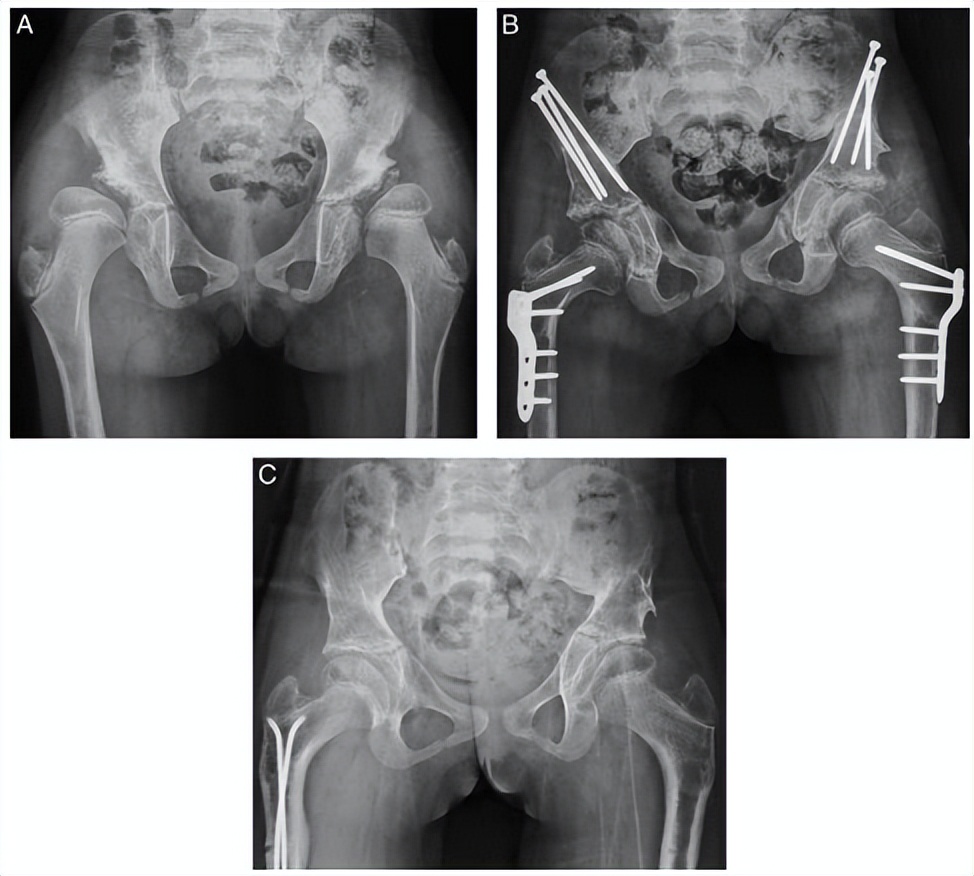

▲ 8岁患儿,双侧儿童髋关节发育不良,外院行切开复位手术后,残留畸形,经“积水潭”微创骨盆三联截骨后,末次随访提示髋关节包容好。